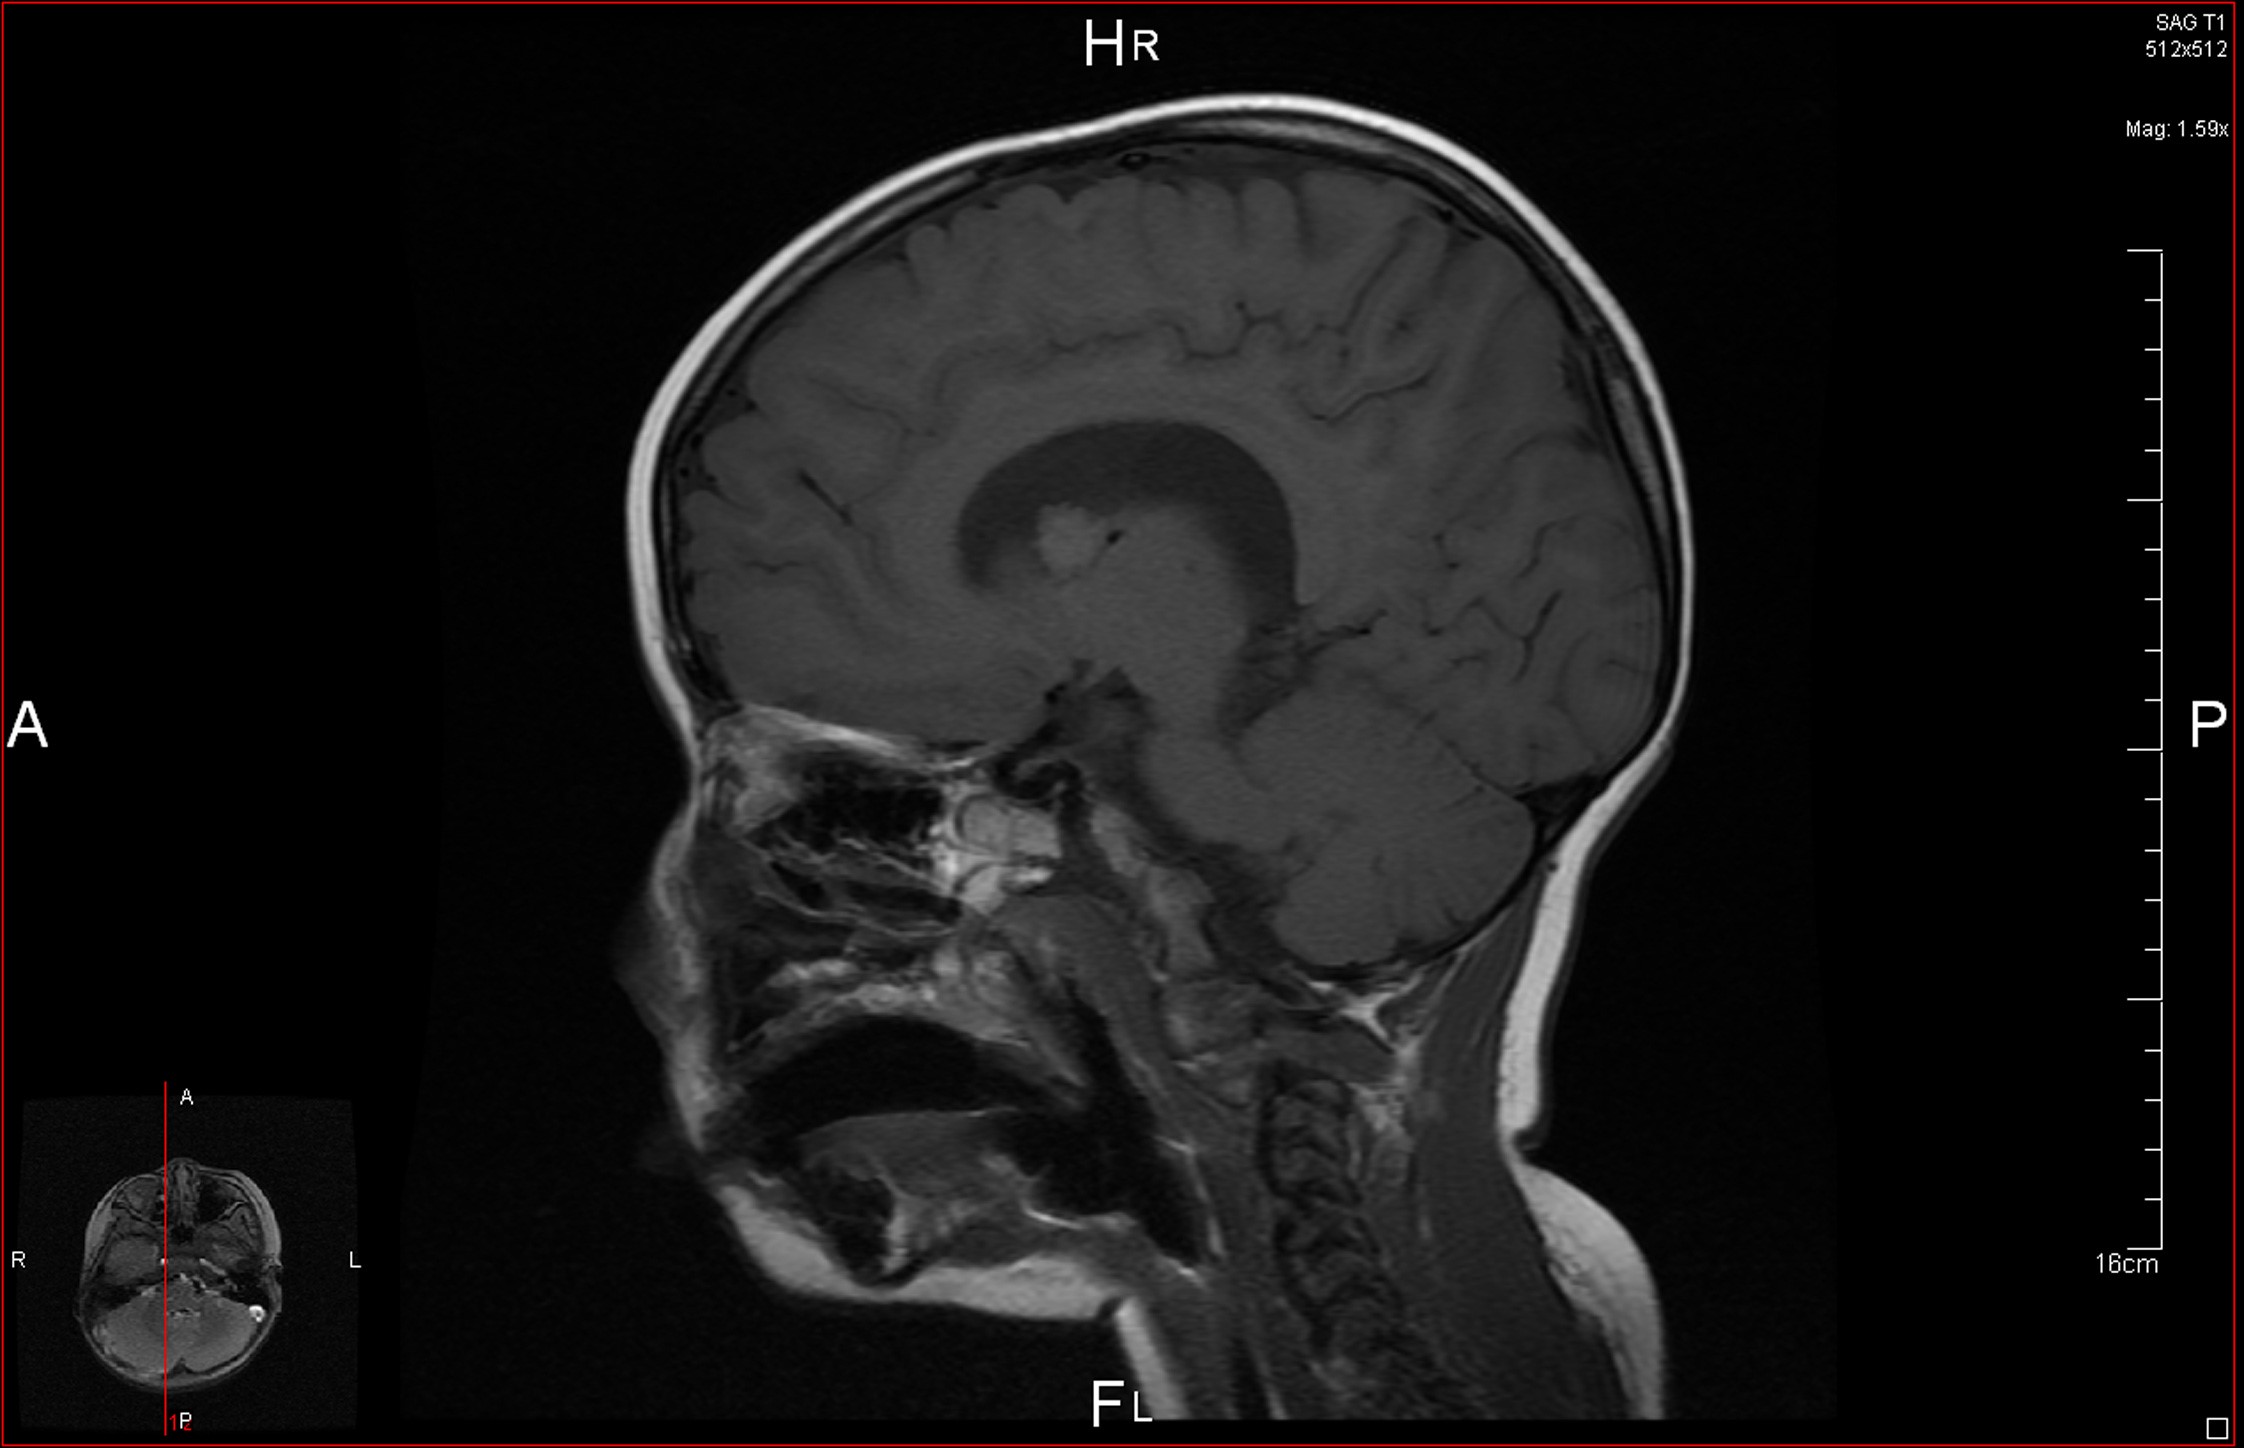

La resonancia magnética (RM) craneal (Fig. 2)muestra una imagen nodular de 11 mm cercana al agujero de Monro derecho, correspondiente a un astrocitoma subependimario de células gigantes (SEGA).

Figura 2. RM craneal: imagen nodular de 11 mm de diámetro cercana al agujero de Monro

• Tumores cerebrales: la lesión cerebral característica es el tuber cortical (hamartomas de la sustancia gris localizados en las circunvoluciones de los hemisferios cerebrales y en la región subependimaria). Pueden calcificarse y protruir en la luz del ventrículo, lo que produce unas imágenes características en “goteo de vela”, u obstruir el agujero de Monro y provocar hipertensión intracraneal. Raramente evolucionan a astrocitomas malignos. El SEGA es característico del complejo esclerosis tuberosa. Todas estas lesiones pueden identificarse mediante TC craneal, especialmente si están calcificadas, siendo la RM más sensible7.